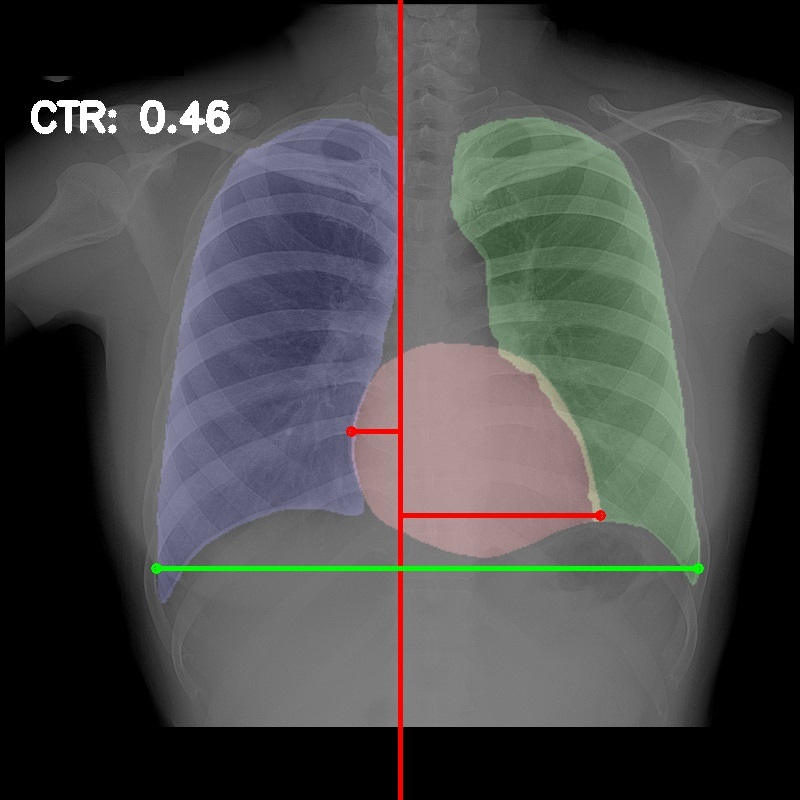

3.5 Cardiothoracic Ratio Calculation

After obtaining the masks, we calculate CTR with equation 1. We calculate cardiac diameter, , by finding the extreme points on the x-axis of the heart mask and calculate their x-axis distance. Thoracic diameter, , is calculated from extreme points from the lung mask. Figure 4 demonstrates the calculation of each component.

After obtaining heart and lung segments, we calculated , , and and marked them on the image along with CTR value calculated from Equation 1.

Figure 6 shows examples of our CTR calculation, where CTR values along with their , and measurement points are correctly identified. In this image, cardiomegaly is correctly detected by CTR value of .